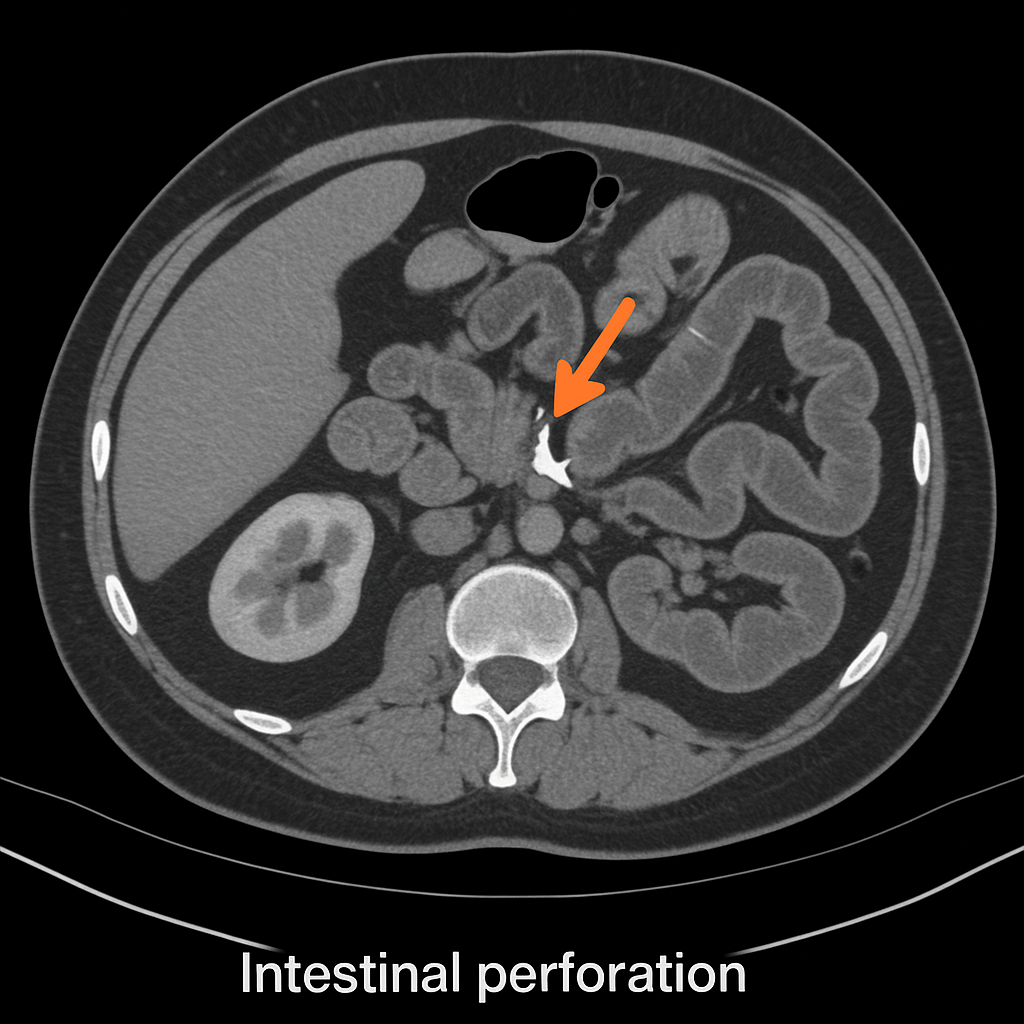

Emergency- Life & Limb Saving Procedures